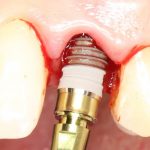

Прежде, чем приступить к аугментации (пластике) лунок зубов, мы подготовили лунки для имплантатов. В таких клинических случаях нет необходимости в использовании шаблона. Вместо этого, мы применяем общепринятые правила позиционирования и соблюдаем рекомендации производителя по хирургическому протоколу:

В процессе ирригации лунки промываются, что позволило нам еще раз подтвердить ранее сделанные выводы. С помощью аналогов имплантатов, входящих в хирургический набор Xive, мы проверили возможность стабилизации имплантатов в будущих лунках. Исходя из правил подбора и позиционирования имплантатов (я очень рекомендую почитать об этом здесь>>) мы остановились на Xive S диаметром 3,4 мм и длиной 13 мм.

Затем уложили ксенографт. Особенностями Bio-Oss Collagen являются удобство адаптации, устойчивость к вымыванию и выдавливанию, поэтому мы просто уложили полученные ранее пирамидки вестибулярно относительно будущего имплантата, после чего прижали их с помощью уже упоминавшихся аналогов имплантата, входящих в хирургический набор имплантационной системы Xive (кстати, при работе с другими имплантационными системами для паковки графта в лунке можно использовать круглые остеотомы для синуслифтинга).

Установка имплантатов

По ряду уже упомянутых выше причин, для решения этой клинической задачи мы выбрали имплантаты Xive. Лунки для них мы уже приготовили. возможную первичную стабильность оценили. Имплантаты мы установили с усилием чуть больше 15-20 Нсм — такого крутящего момента более, чем достаточно, особенно если учесть, что временные коронки будут соединяться между собой.

Подробно о том, что такое крутящий момент и хирургический протокол можно прочитать здесь>> и тут>>, соответственно. Из-за использования специальных индивидуализируемых временных абатментов, имеющих только три положения, нам нужно позиционировать платформу имплантатов по граням. Это очень просто  — мы выводим вырез абатмента TempBase (он входит в комплект поставки) вестибулярно.